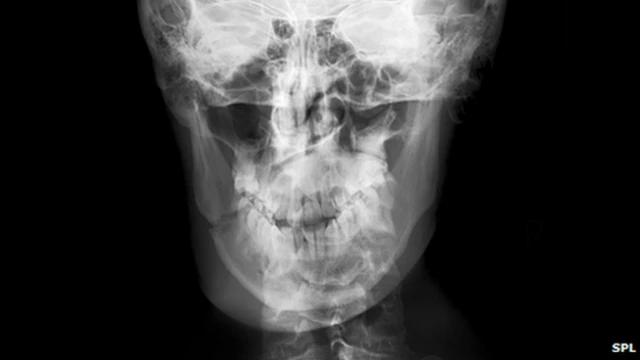

ایک نئی تحقیق میں کہا گیا ہے کہ ہمارے مرد آبا و اجداد نے مکے سے بچنے کے لیے چہرے کے موٹے نقوش اختیار کیے۔

اس تحقیق میں مزید کہا گیا ہے کہ جو ہڈیاں چہرے پر مکہ کھانے کے باعث ٹوٹتی ہیں، وہ بھی ارتقا کے عمل سے گزر کر زیادہ مضبوط ہوئیں۔

تحقیق کے مطابق یہ وہ ہڈیاں ہیں جو مردوں اور عورتوں میں بہت مختلف ہیں۔